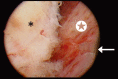

Lower urinary tract symptoms (LUTS) secondary to benign prostatic hypertrophy (BPH) are among the most common medical issues for aging men. Population-based studies suggest that 13.8% of men in their 40s and more than 40% of men over age 60 have BPH. When LUTS are refractory to medical therapy and bothersome enough to warrant surgical intervention, transurethral resection of the prostate and open simple prostatectomy have been the historical reference-standard procedures for decades. Both procedures are highly effective and offer durable improvements in urinary functional outcomes. However, they also have the potential for considerable perioperative complications and morbidity. In an effort to limit surgical morbidity, a variety of minimally invasive surgical techniques to treat BPH have been introduced. Herein we present a comprehensive, evidence-based review of the efficacy and safety profile of modern minimally invasive treatments for large-gland BPH.